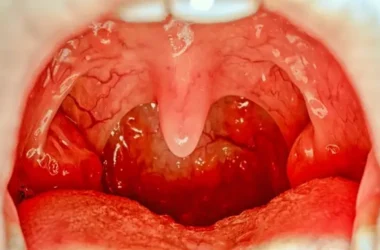

من الضروري جداً معرفة متى تتجاوز حساسية الطعام مرحلة العلاج المنزلي وتتطلب تدخلاً طبياً طارئاً. لا تتردد أبداً في طلب المساعدة الطبية الفورية إذا ظهرت عليك أو على أي شخص علامة واحدة أو أكثر من الأعراض التالية، لأنها قد تشير إلى رد فعل تحسسي شديد (تأق):

- صعوبة في البلع أو شعور بانسداد الحلق.

- انتفاخ واضح في الوجه، الشفتين، اللسان، أو العينين.